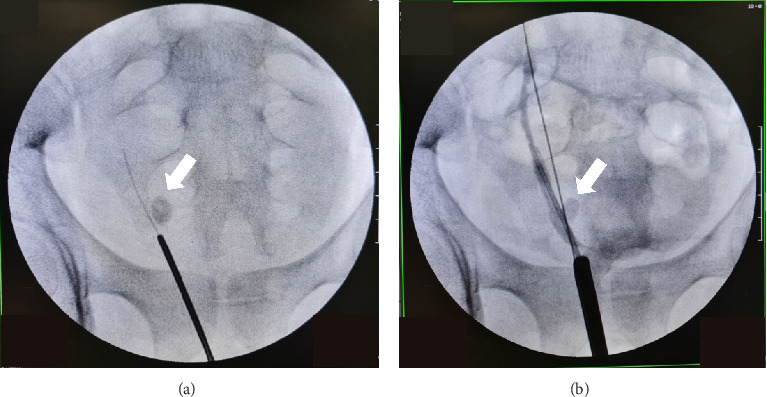

双肾,虽然相对罕见(发生在1%-4%的病例中),但当与尿路症状相关时,可构成重大的临床挑战。需要干预的并发症包括结石形成、尿路梗阻和反流疾病。我们报告一例22岁男性右肾完全双侧伴输尿管远端结石引起的上段肾积水,经超声诊断并术中逆行肾盂造影(RPG)证实。最终通过输尿管镜(URS)碎石术治疗。

Duplex kidneys, though relatively uncommon (occurring in 1%-4% of the cases), can pose significant clinical challenges when associated with urinary tract symptoms. Complications requiring intervention include stone formation, urinary obstruction, and reflux disease. We present the case of a 22-year-old male with complete duplex right kidney with upper moiety hydronephrosis due to a distal ureteral stone, diagnosed by ultrasonography and confirmed with intraoperative retrograde pyelography (RPG). Definitive management was achieved via ureteroscopy (URS) lithotripsy.